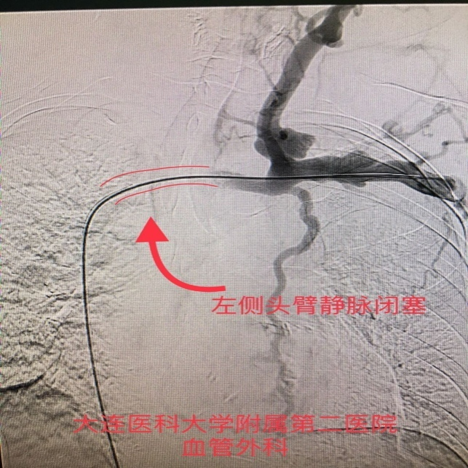

手术过程:造影证实为左侧头臂静脉闭塞。经球囊扩张成形术后,症状完全缓解,内瘘恢复正常使用。

图:造影证实左侧头臂干静脉闭塞

术前造影

术中造影

图:术中造影